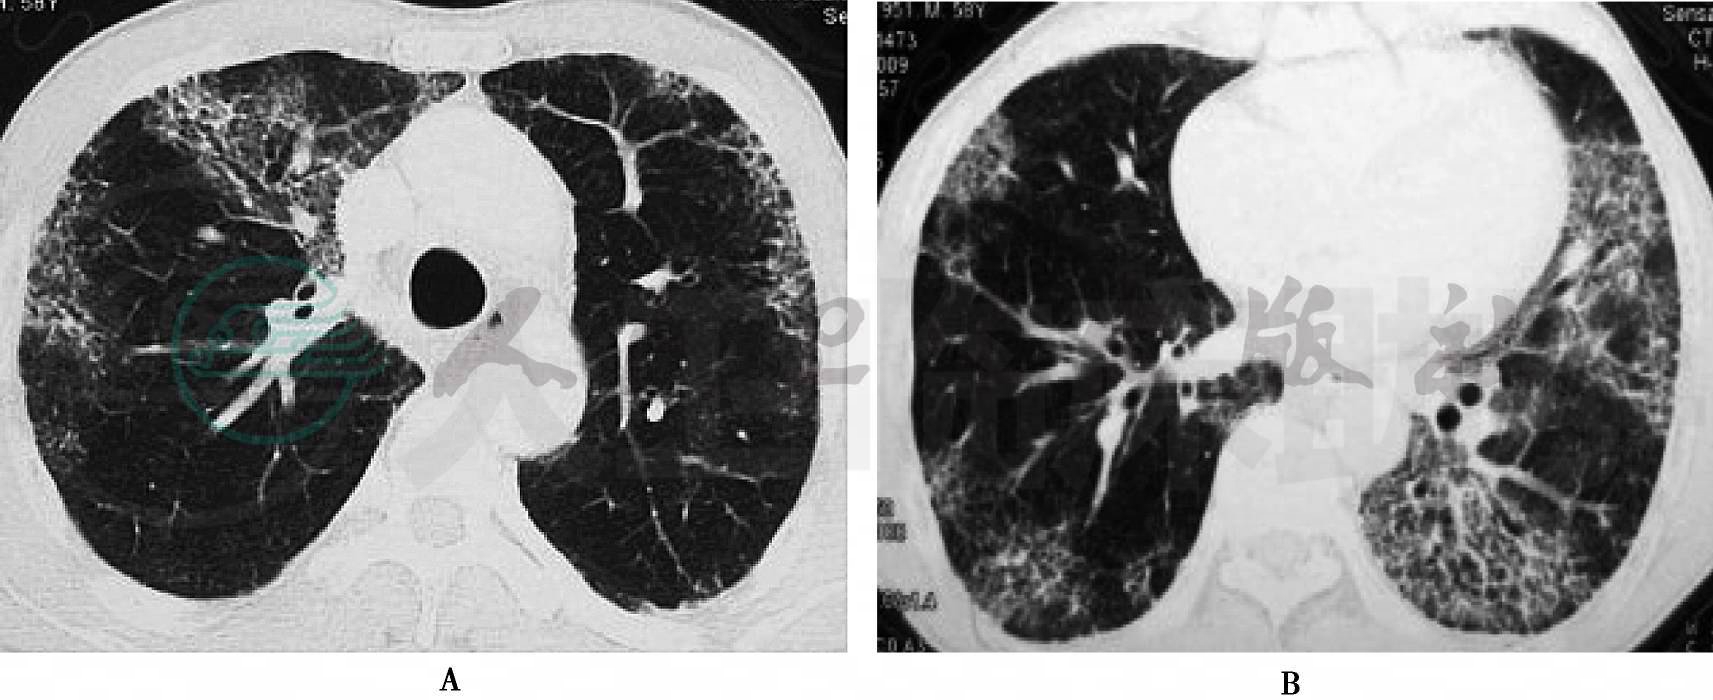

患者,男性,50岁,司机,系病例1患者的弟弟。主因“咳嗽,胸闷气促3年,加重伴发热6天”于2012年4月19日收住我科。患者3年前,无明显诱因出现阵发性咳嗽,痰少,干咳为主,活动后胸闷,无胸痛、发热等。2009年曾在我院门诊就诊,诊断为“双肺间质性肺炎”,但患者未予重视及规范治疗。上述症状逐渐加重。2011年7月13日在我院门诊就诊,行肺部CT(图3)示双肺间质病变,寻常型间质性肺炎(UIP)可能性大,诊断为“特发性肺纤维化”,予以口服泼尼松30mg/d,1个月后症状无明显改善,患者自行停药。2012年1月,患者到广州就诊后,再次服用泼尼松30mg/d,1个月。入院前6天,患者受凉后,咳嗽咳痰、胸闷较前明显加重,咳较多白色黏液痰,痰中偶有少量血丝。轻微活动后即感明显气促。伴发热,体温波动在37.5℃左右,并停用激素治疗。无胸痛、脱发畏光、关节肿痛等。患者自起病来,精神、睡眠差,饮食尚可,二便正常。既往史:10年前患有肺结核,已治愈,余无特殊。个人史:吸烟20年、40支/天,饮酒20年、白酒1斤/天,烟酒已戒3年。

图3 肺CT(2011-07-11)

肺部CT(图4):双肺弥漫性斑片状影,间质性肺炎改变,双上肺肺大疱,纵隔内及双肺门多发淋巴结肿大,双侧胸膜增厚粘连。

图4 肺CT(2012-04-20)

入院后查看患者既往肺部高分辨CT(HRCT),符合UIP,间断服用激素,效果不佳,症状逐渐加重,追问病史,无药物、职业、结缔组织相关病史,结缔组织疾病相关抗体检查阴性,UIP诊断明确。因一个家族两个患者相继发病,诊断为“家族性特发性肺纤维化”。此次受凉后,原发症状加重,咳痰多,发热,血象升高,复查肺部CT(图5)示新发渗出病变,考虑原发病合并社区获得性肺炎。入院后予以无创呼吸机辅助呼吸,美洛西林/舒巴坦2.5g每8小时一次、阿奇霉素0.5g每天一次抗感染,N-乙酰半胱氨酸抗纤维化治疗5天后,患者病情无明显好转,体温较前升高,考虑感染未控制,改为美罗培南1.0g每8小时一次、替考拉宁0.4g每天一次抗感染,考虑肺间质病变患者,有长期使用激素病史,为感染高危者,易合并真菌感染,同时予以伊曲康唑0.25g每天一次抗真菌治疗,体温较前稍有下降,但气促症状明显,遂于5月2日起予以甲泼尼龙80mg静滴抗炎治疗。上述症状无明显改善,患者家属于5月12日要求签字出院。